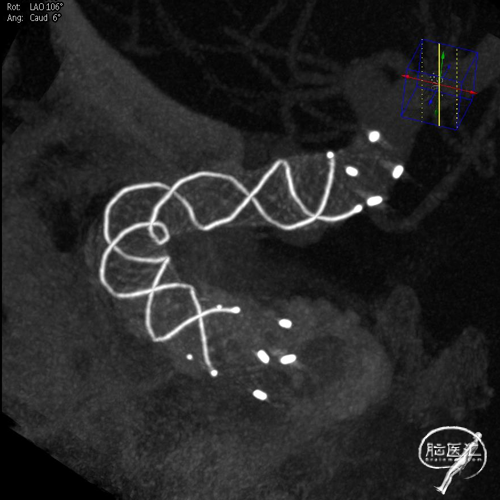

术后3D造影及支架重建,可见支架展开和贴壁良好。

术后影像。